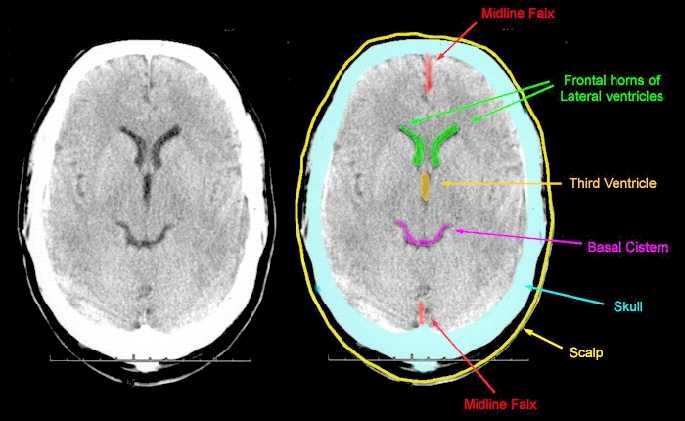

3. Identify normal anatomical features of the brain on images produced by CT and MRI scanning

1. CT Scan

1. MRI scan